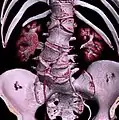

Congenital block vertebra of the lumbar spine. CT volume rendering.